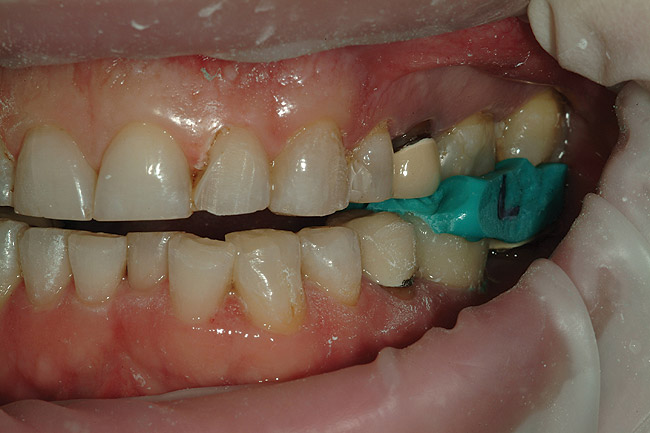

Figure 34  After isolating the preparations from moisture using a latex-free rubber dam and blue mouse, the restorations were ready to be inserted.

Figure 34